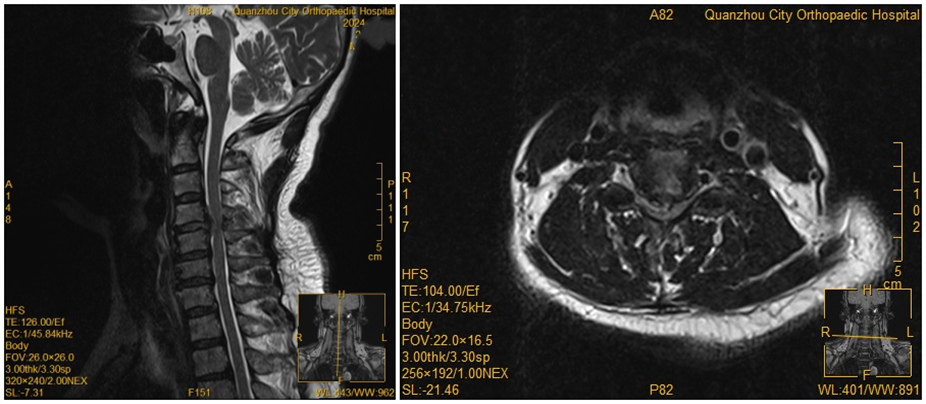

[颈椎病] 【正骨技术】精准高效!显微镜下颈椎前路手术助力患者加速康复 日期:2024-12-05 10:27:00 点击: 好评:0